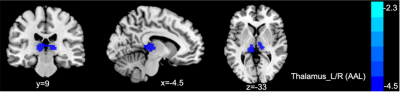

Keywords: Neurodegeneration, fMRI, Structural MRI We aim to study structural and functional changes over time with a focus on the thalamus and hippocampus regions of interest. Longitudinal analysis was performed in N=274 UK Biobank participants. We find strong correlations between the baseline and follow-up MRI readouts. Namely, it is possible to predict thalamus and hippocampus volume changes across a mean of 2.25 years using baseline volume and resting state functional activation estimates. This work helps characterizing the longitudinal consistencies within both hippocampal and thalamic MR readouts and helps setting up prediction models as the next step. |